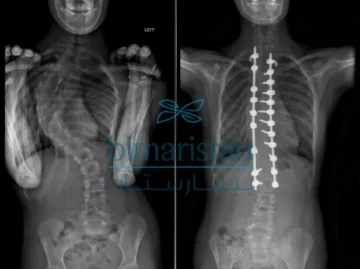

متى تحتاج زاوية كوب في اعوجاج العمود الفقري للجراحة؟ دليل مبسّط للأهل يُعد تشخيص اعوجاج العمود الفقري لحظة مليئة بالأسئلة والقلق لدى المرضى والأهل، ويبرز من بينها سؤال محوري يتكرر كثيرًا: عند أي درجة

متى يحتاج مريض اعوجاج العمود الفقري للجراحة؟ العلامات والأعراض التي يجب أن تعرفها…

متى يحتاج مريض اعوجاج العمود الفقري للجراحة؟ العلامات والأعراض التي يجب أن تعرفها يُعتبر اعوجاج العمود الفقري (Scoliosis) من المشكلات الشائعة التي تثير قلق الأهل عند اكتشافها لدى أبنائهم. ورغم أن معظم الحالات يمكن